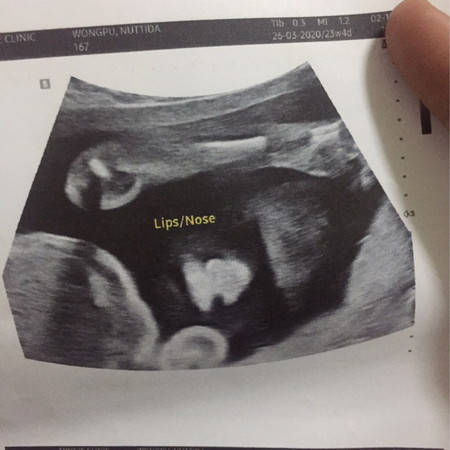

ปากแหว่งดูยังไงคะ

แบบนี้น้องปากแหว่งไหมคะ มันมองเห็นไหม

ต้องถามหมอค่ะ หมอเราจะซาวด์ดูความผิดปกติให้ทุกเดือน ตามการเจริญเติบโต หมอเคยบอกว่า ปากแหว่งสามารถซาวด์แล้วเห็นความผิดปกติได้ แต่เพดานโหว่เด็กบางคนไม่สามารถซาวด์เห็นได้พึ่งมารู้ตอนคลอดก็มีค่ะ

อ่านเพิ่มเติมต้องถามหมอจ้าแม่ ถ้าอยากเห็นชัดๆต้องซาวด์แบบ4มิติ

ดูที่รูป2 ไม่แหว่งนะคะแม่

ไม่แหว่งค่ะ